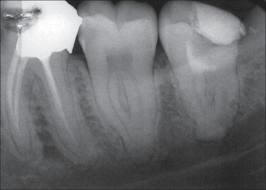

Rx de

molares inferiores mostrando la

disposición de las raíces y sus

conductos. |